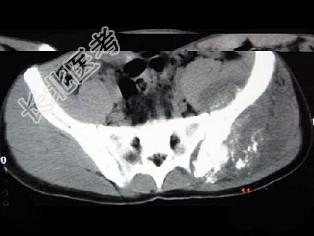

- 单项选择题男,35岁, 左髂部剧烈疼痛,尤以夜间明显, 可摸到肿物,结合图像, 最可能的诊断是 ( )

A、骨巨细胞瘤

B、软骨肉瘤

C、骨转移瘤

D、骨肉瘤

E、软骨瘤